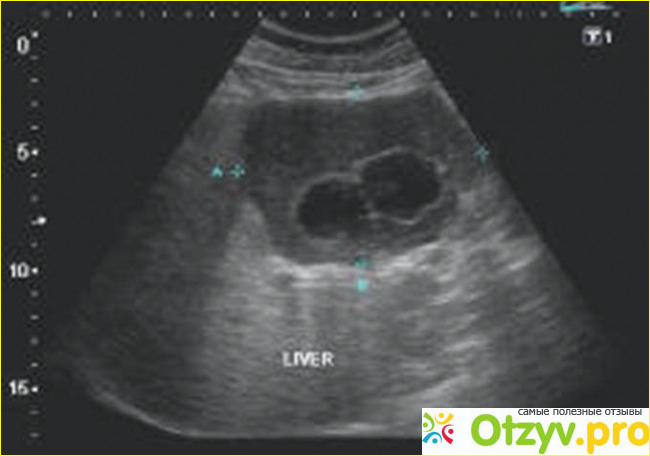

или вообще любые незначительные. Такая диагностика должна проводиться в клинике. под руководством вашего лечащего доктора или же даже самим вашим лечащим доктором. Скажу сразу. если вы не уверены в знаниях вашего лечащего специалиста либо у вас есть к его знанию какие-либо вопросы претензионного характера. то. конечно же. я вообще бы не рекомендовала идти на прием к такому "специалисту". чтобы не рисковать своим здоровьем. Но обследоваться все-равно нужно. Прежде чем делать какую-либо диагностику внутренних органов. обязательно нужно сдать все необходимые анализы. А направление на сдачу этих анализов вам должен написать в вашей клинической больнице ваш лечащий доктор. Ультразвуковые исследования довольно популярны на сегодняшний день. потому что они дают возможность более качественно рассмотреть интересующие вас (или вашего врача) внутренние органы. посмотреть. все ли в них в порядке. нет ли в вашем организме каких-нибудь патологий на любом этапе возможности ихнего проявления. Ультразвуковой метод осмотра появился уже достаточно много лет назад. но все равно он был и остается одним из самых популярных даже на современном уровне прогрессирующего развития в медицинской науке. Касательно ультразвукового обследования человеческого организма. узи органов брюшной полости человека и печени проводится более часто. чем обследования других жизненно важных органов. Это и понятно. потому что в наше столь нелегкое время каждому человеку должно быть известно. что такое печень. и главная функциональность этого органа человеческого организма. Ведь благодаря этому жизненно важному органу и его столь широкой функциональность происходит фильтрация всех качественных и не качественных продуктов питания. обезвреживание всех тех токсических веществ. которые каким-то образом попали в наш организм через пищеварительный тракт. также через печень происходит и фильтрация крови и . конечно же. регулирование липидов в составе крови.